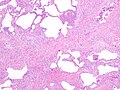

UIP - fibrosis - low mag. (WC)

Microscopic

Features:[6]

- Fibroblast foci:

- Interstitial inflammation.

- Microscopic honeycombing.

- Typically peripheral - cysts lined by ciliated epithelium.

- Spatial heterogeneity - patchy lesional distribution (areas of abnormal and normal lung may appear beside one another).

- Temporal heterogeneity - lesions of differing age side-by-side.[9]